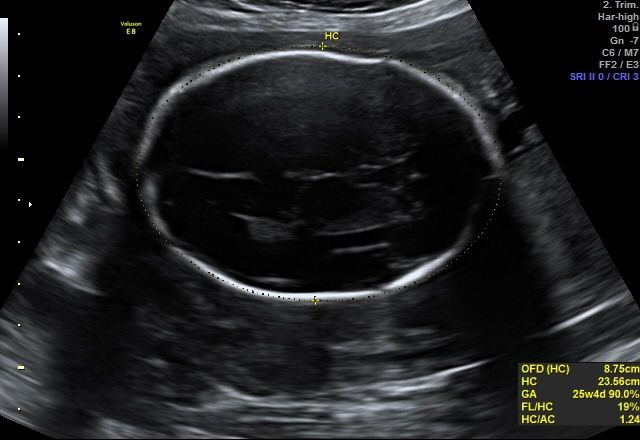

Овальная голова плода. Часть 2

Лекса @_SS_industry, я знаю, что она должна быть овальной. Это мой третий ребенок. Но, она вытянуто овальной формы. Я просто очень переживаю, так как это может быть долихоцефалия((

Victoria Sever, у нас она вытянутой формы, потому и показывает опережение.. именно от лба до затылка у нас она на 2 недели больше срока..

Витаминка, я знаю, что она должна быть овальной. Это мой третий ребенок. Но, она вытянуто овальной формы. Я просто очень переживаю, так как это может быть долихоцефалия.